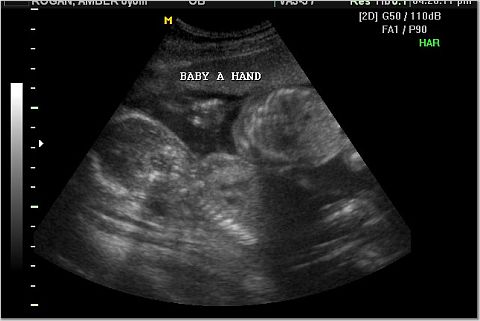

Baby A was the active one. Here is her profile and her hand.